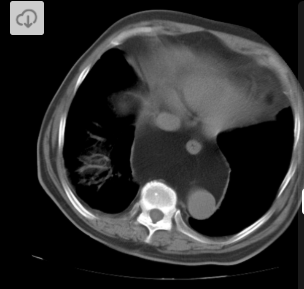

2 anos, masculino

Cisto de duplicação esofágico

Predleção por meninos; diagnosticados na infância

Em geral assintomáticos; podem provocar estridor

Mais comuns no esôfago distal; geralmente não comunicam com a luz do esôfago;

TC: Cisto com densidade de líquido, margens bem definidas que podem realçar com contraste; podem complicar com hemorragia, infecção: nível liquido, espessamento parietal.